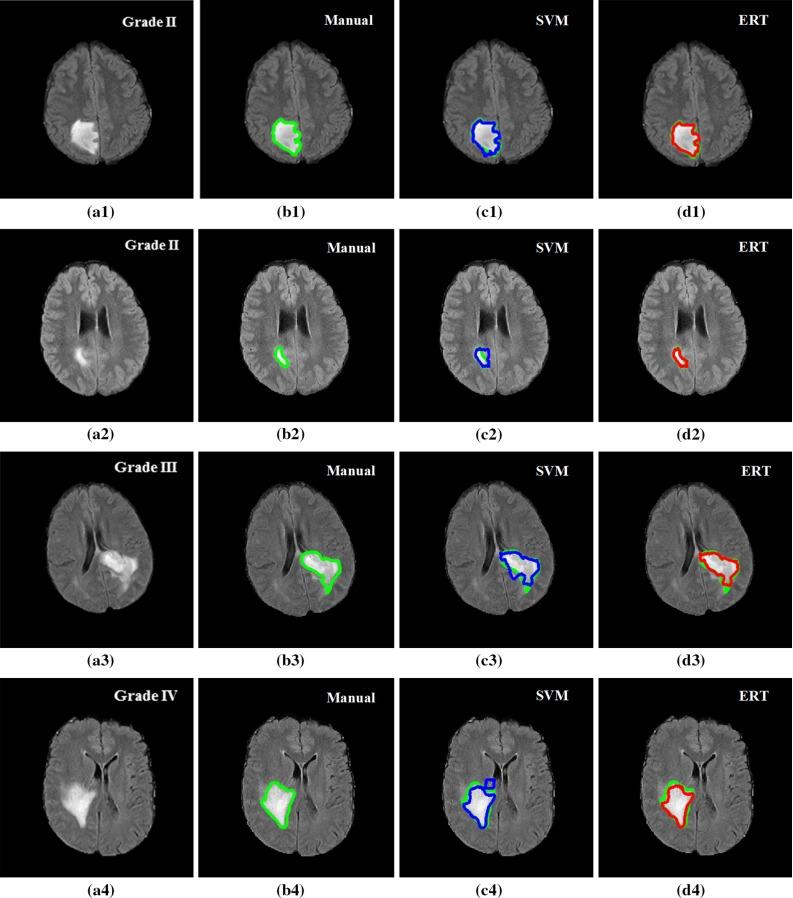

The method is based on superpixel technique and classification of each superpixel. A number of novel image features including intensity-based, Gabor textons, fractal analysis and curvatures are calculated from each superpixel within the entire brain area in FLAIR MRI to ensure a robust classification. Extremely randomized trees (ERT) classifier is compared with support vector machine (SVM) to classify each superpixel into tumour and non-tumour.

The proposed method is evaluated on two datasets: (1) Our own clinical dataset: 19 MRI FLAIR images of patients with gliomas of grade II to IV, and (2) BRATS 2012 dataset: 30 FLAIR images with 10 low-grade and 20 high-grade gliomas. The experimental results demonstrate the high detection and segmentation performance of the proposed method using ERT classifier. For our own cohort, the average detection sensitivity, balanced error rate and the Dice overlap measure for the segmented tumour against the ground truth are 89.48 %, 6 % and 0.91, respectively, while, for the BRATS dataset, the corresponding evaluation results are 88.09 %, 6 % and 0.88, respectively.

在两个数据集上对所提出的方法进行了评估:(1)我们自己的临床数据集:19例II至IV级胶质瘤患者的MRI FLAIR图像,以及(2)BRATS 2012数据集:30张FLAIR图像,其中有10例低级别胶质瘤和20例高级别胶质瘤。实验结果表明,使用ERT分类器的所提出方法具有较高的检测和分割性能。对于我们自己的队列,分割肿瘤相对于真实情况的平均检测灵敏度、平衡错误率和Dice重叠度量分别为89.48%、6%和0.91,而对于BRATS数据集,相应的评估结果分别为88.09%、6%和0.88。